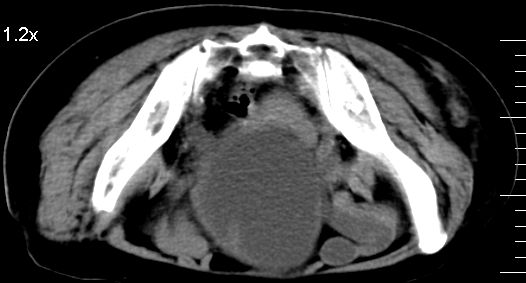

补充一下,谢谢提醒!

1.膀胱后壁见不规则致密影,随体位改变,为膀胱内凝血块;

2.双侧输尿管下段扩张.输屎管结石可能大。建议作进一步检查。

2.双侧输尿管下段扩张.输屎管结石可能大。

双侧输尿管下端扩张,并膀胱内血凝块 输尿管下端结石

2.双侧输尿管下段扩张,临床有血尿病史,建议进一步检查,找出血原因。